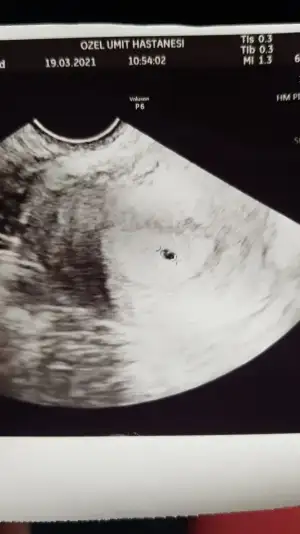

Daha önce yazmıştım ama mesajı şansa gördüm yazmadan geçemedimKızlar hamile olanlar belirtilerini neler yaşadıklarını ekstra neler yaparak hamile kaldıklarını yazabilir mi Mart ayında sanki vardı öyle bişey burda da olursa bizler içinde iyi olur onları bi yere sabitlesek herkes ordan okuyabilir

Bende yumurtlama çatlama vs bittikten 3-4 gün sonra akıntı başladı renksiz adet tarihime kadar sürdü nerdeyse.Ve en belirgin ikinci belirtim yine çatlamadan 3-4 gün sonra adetten bir kaç gün önce olan adet ağrılarım olmaya başladı, akıntıylada birleşince kaç kere adet oldum heralde diye lavaboya gittim

Bir gece göğüslerim tıpkı sezeryandan sonra bebeğimi kaybettiğim için sütlerim birikmişti benim ,aynı öyle acıdı ateşlendi bir kaç saat sürdü ama .Benim mide bulantısı koku hassasiyeti sık idrar filan olmadı ..Umarım yardımcı olmuşumdur ..Hepiniz dualarımdasınız